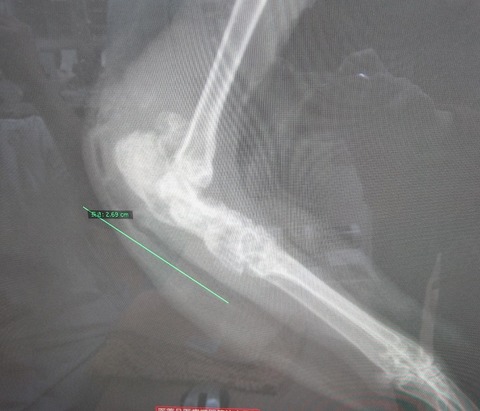

右足患部のレントゲン

本来、かかとの辺り、この部分の骨はこういった状態です。

びっくりしたわ! クロちゃんの骨、全然むちゃくちゃやん! て。

重度だったので潰瘍が骨まで浸食し、骨の中に入りこみ擬化して形成されてる。

…みたいな説明やったと思います(;´Д`)

炎症止めなど投与しているので、侵食されてる骨に痛み等はもうないはず。

表傷が治っても、骨の形成はそのままですが、

骨折しやすいとか、そういった問題を抱えてるわけでもないようです。